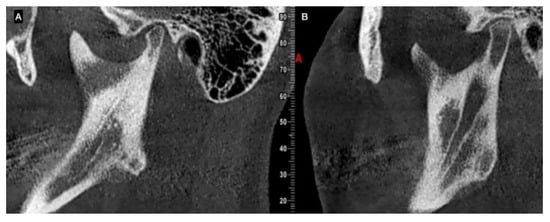

| CBCT | Augmentation in condylar size in comparison to the non-hyperplastic condyle |

| Lack in upper cortical line of the affected condyle in the upper area showing an active metabolism | |

| Augmentation in radiolucency in the affected condyle with an image related to poor density in some cases | |